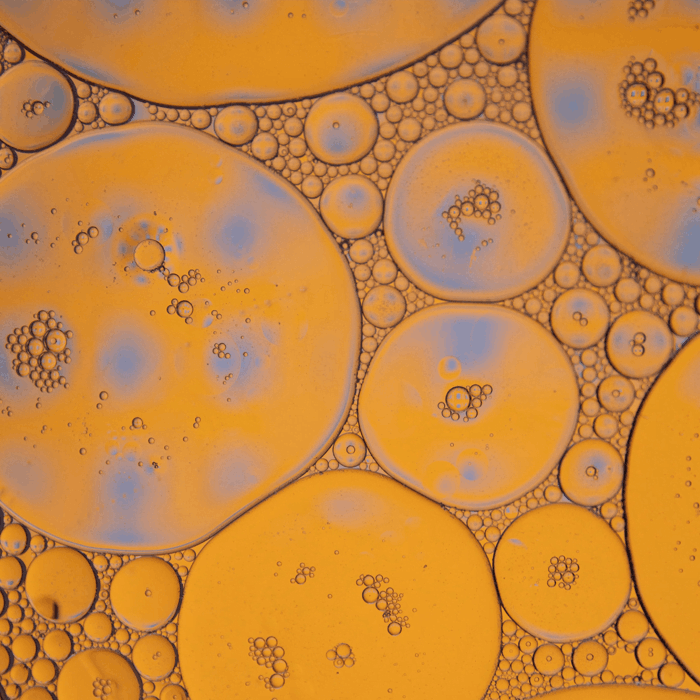

Lipoprotein(a) ist eine fett- und eiweisshaltige Substanz im Blut. Erhöhte Werte können mit einem erhöhten Herz-Kreislauf-Risiko in Zusammenhang stehen. Im Gegensatz zu anderen Blutfetten wird die Konzentration von Lipoprotein(a) weitgehend genetisch bestimmt und ist nur begrenzt durch Lebensstilfaktoren beeinflussbar.